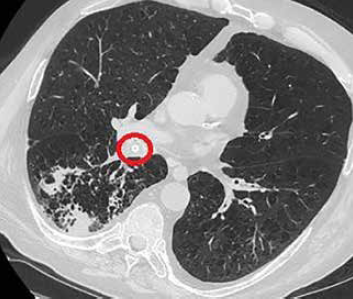

Si sottoponeva intanto ad una TC del torace senza mdc che mostrava enfisema polmonare diffuso bilateralmente, confermava la presenza di multiple consolidazioni polmonari a carico del LID ed evidenziava stenosi del bronco lobare inferiore di destra da parte di materiale iperdenso (Figura 1).

Figura 1.La TC del torace senza mdc mostrava multiple consolidazioni polmonari a carico del LID ed evidenziava stenosi del bronco lobare inferiore di destra da parte di materiale iperdenso.